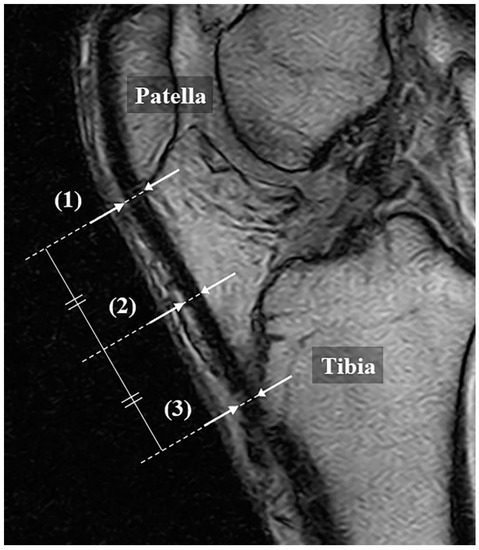

MRI was performed using a 0.18-T extremity MRI device C-Scan (Esaote S.p.A, Genova, Italy). As with the US measurement, the patients were placed in a supine position, with a knee flexion of 30 degrees. The scan was performed according to the knee protocol set by the device, with a sagittal gradient echo (matrix 288 × 200; repetition time (TR) 580, msec/echo time (TE) 16 msec; field of view 190 mm; slice thickness 4.0 mm; flip angle 75 degrees). In the slice at the center of the patellar tendon, the tendon thicknesses were measured at the same points as those measured with US (Figure 2). The measurements were performed by 2 orthopedic surgeons with the images anonymized, and the average value was used.

Figure 2. Measurement method of patellar tendon with MRI (gradient echo, sagittal). Thickness is defined as the distance from the superficial to the deep layers of the tendon at (1) the proximal part, (2) the midpoint, and (3) the distal part, respectively. This follows the method explained in Figure 1 for the ultrasonography.